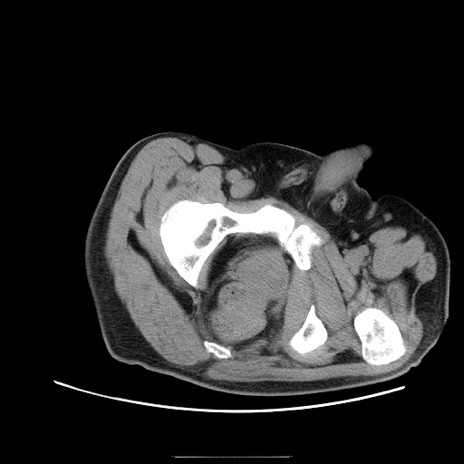

症例22(横断像)

【症例】50歳代男性

【主訴】腹痛

【現病歴】AVMからの被殻出血のため回復期リハ病棟入院中。 本日午後3時頃急に下腹部痛が出現した。

【既往歴】AVM、被殻出血、虫垂炎、高血圧

【身体所見】意識晴明、左半身不全麻痺、会話の理解は良好、36.5°C、腹部:膨隆、全体に板状硬、下腹部正中に圧痛点あり、反跳痛-、筋性防御不明、右下腹部にope scar

【データ】WBC 9400、CRP 0.06